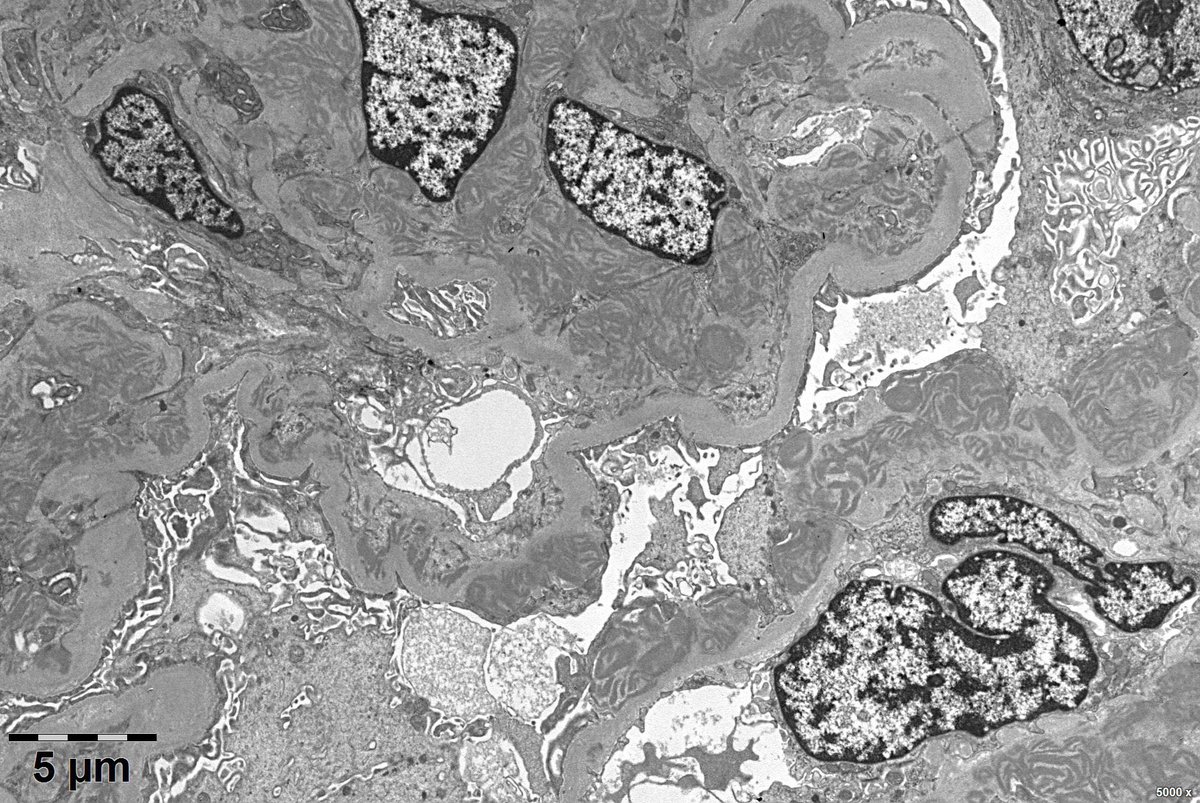

Friday brainstorming! Another case. 40 yr male, S. Creat-4.9 mg. What do you think it can be?? PG residents-Have a look! Renal Path Labs quiz @RenalPathLabs #RenalPath #AskRenal #AskrenalPath #RenalPathSociety See u all on Monday with some discussion!

@RenalPathLabs @Ask_Renal @AskRenalPath @Renalpathsoc Case 1 granular deposits along capillary basement membrane case 2 linear deposits along basement membrane, in addition with crescents. Case 2 anti GBM disease. Case 1 MGN

@Venkateshgilly2 @Ask_Renal @AskRenalPath @Renalpathsoc Correct, in addition case 1 also having Diabetes, had nodules, staining around TBM seen in picture.